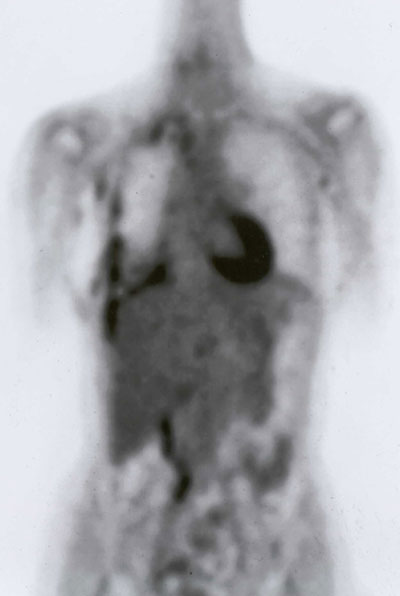

Radiological evaluation is essential to determine if a patient with MPM has potentially resectable disease. Posteroanterior and lateral chest roentgenogram (Figure 1), computerized tomography (CT scan) of the chest and upper abdomen (Figure 2), and magnetic resonance imaging (MRI) of chest have been the most widely used modalities. CT scan provides an estimate of tumor burden and extent of tumor both locally and distantly. MRI can supplement the CT scan for detection of tumor extension into the mediastinum or the abdomen. More recently, positron emission tomography (Figure 3) has been used to determine if a patient has early resectable disease based on no evidence of contralateral disease or distant metastasis. Early results are promising [6].